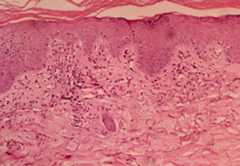

Histological findings of dermatomyositis:

Vacuolar changes of columnar epithelium and lymphocytic inflammatory infiltrate at the dermal-epidermal interface are found in dermatomyositis.